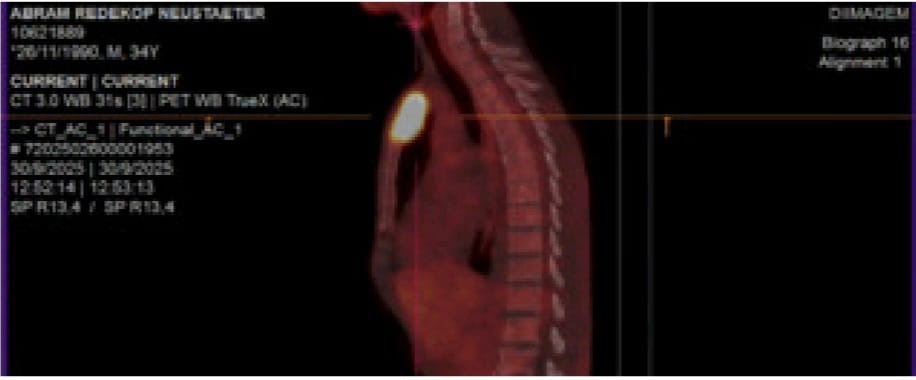

A new update on Abram He never got to implant his jawbone because he has three new tumors which you can find in the picture gallery. One on the other side jawbone, one on his chest one in his lung,He is now taking chemotherapy. in Brazil. ABRAM and his wife and family are in urgent need of our prayers and support. May God bless every prayer and support